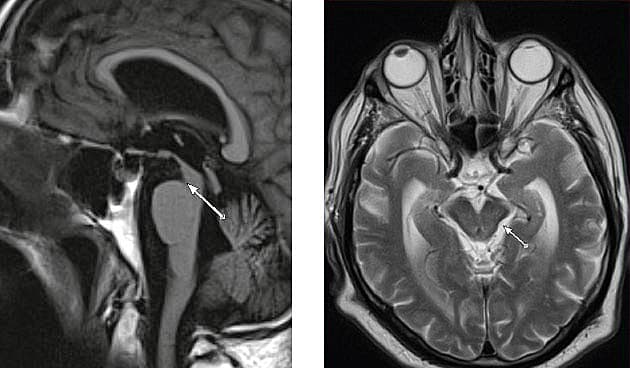

En 67-årig mand med følger i form af synkebesvær efter larynxcancer blev indlagt akut med faldtendens og bilateral oculomotoriusparese. Han havde haft kognitiv funktionsnedsættelse med snigende debut og parkinsonistiske symptomer i flere måneder. Ved en objektiv undersøgelse fandt man vertikal blikparese, specielt ved blik nedad, langsomme øjenbevægelser, nedsat blinkefrekvens og nedsat følgebevægelser af øjnene. Der var samtidig langsom bevægelighed, rigiditet, specielt aksial rigiditet og tiltagende usikker gang. Talen var hypofon og dysartrisk. Baseret på de kliniske fund blev der rejst mistanke om progressiv supranukleær parese (PSP). Diagnosen blev støttet af resultaterne af en MR-skanning af cerebrum. MR-skanning hos patienter PSP afslører betydelig atrofi af mesencefalons tegmentum med relativ bevarelse af pons, kendt som »kolibritegn« (A) [1]. »Kolibritegnet« er nyttigt ved skelnen af PSP fra Parkinsons sygdom og multisystematrofi [2, 3]. Ved MR-skanning hos patienter med PSP finder man også andre, mindre typiske tegn som »Mickey Mouse-tegn« (B). Dette ses typisk som en reduktion af mesencefalons anterio-posterior-diameter og udtynding af cerebrale pedunkler [3, 4]. MR-skanning er primært en hjælp ved PSP til udelukkelse af andre differentialdiagnoser som multipel systematrofi, kortikobasal degeneration og multiinfarktdemens.